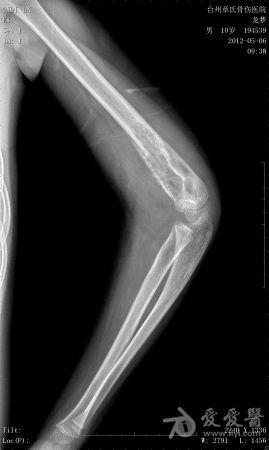

年龄:10岁主诉: 右上臂疼痛活动受限20余天现病史: 20余天前摔伤致右肘部疼痛活动不利,曾在外院治疗,X线:右肘部未见明显异常。肘关节活动尚可,于活血化瘀,消肿止痛治疗。20余天疼痛未见明显好转,肘关节活动不利,***就诊。既往史: 既往健康

体格检查: 一般状况好,发育良好,营养中等。头颅五官胸腹未见异常。右肘部,右上臂下端肿胀,压痛、纵向叩击痛(+),局部肤温增高。肘关节固定于约40°,背伸约20°,肘屈约100°,表面无血管充盈,无色素沉着。右上肢皮肤感觉正常,右桡动脉搏动正常。

初步诊断: 左肱骨下端骨肿瘤X线检查显示左肱骨中上段有虫蚀样 低密度改变,局部硬化,可见骨膜反应,病理性骨折鉴别诊断: 动脉瘤样骨囊肿,骨结核诊疗过程:

讨论内容:患者病史极短,摔伤后检查未见明显异常,初次就诊,复诊时间间隔约16天,未留下初次就诊的X线资料,仅感觉肱骨下端较上段骨密度稍减低。

骨肉瘤多见于小儿,多发生于干骨端,常见于股骨远端和胫骨近端。骨肉瘤的X线表现:⒈骨质破坏⒉肿瘤骨⒊肿瘤软骨钙化⒋软组织肿块⒌骨膜反应和Codman三角。动脉瘤样骨囊肿多发生于10-20岁,可发生生于长骨和脊柱。动脉瘤样骨囊肿的X线表现为长骨干骺端的溶骨性、偏心性骨破坏,其偏心向外突出如气球状膨胀,病变呈局限性透亮区,边界清楚,边缘有狭窄的硬化带,其中有不规则的分隔,呈蜂窝状。位于骨中心者,向周围扩张膨胀,呈卵圆形,与骨的纵轴一致。囊肿表面有一薄的骨壳,可有一层薄的骨膜反应。位于脊椎的病变多在脊突、椎板、横突上,亦可膨出于骨外。 根据以上特点和本病例的表现,骨肉瘤可疑。